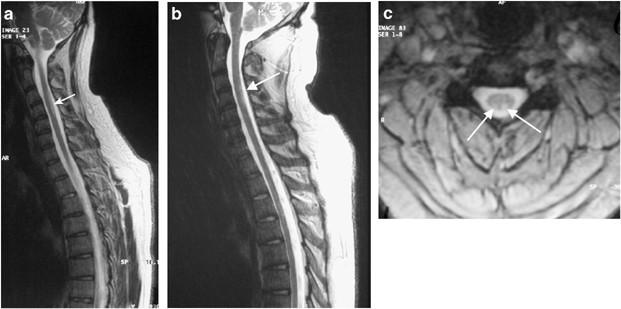

Cerebro Spinal Decompression Sickness Report Of Two Cases Spinal Cord